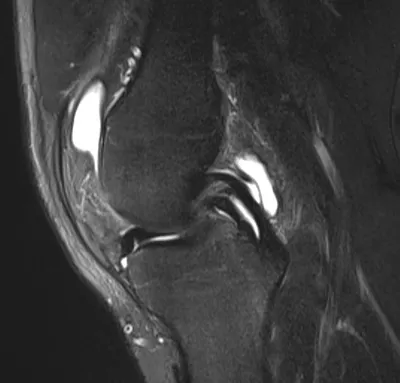

Posterior meniscocapsular ligament injury

MRIKneeSagittal+2

4/23/2026